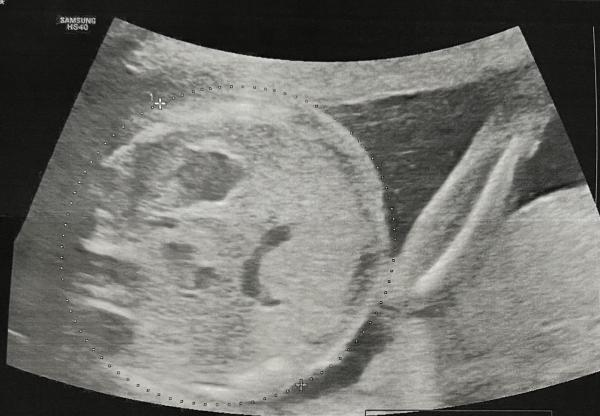

Hallo zusammen, war heute beim großen Ultraschall. Ich habe nicht viel erkannt weil das Baby nun doch schon ziemlich groß ist. im Auto sehe ich dann dieses Bild im Mutterpass. Das Gesicht?! Es sieht irgendwie sehr eindeutig aus aber irgendwie auch sehr komisch oder nicht?